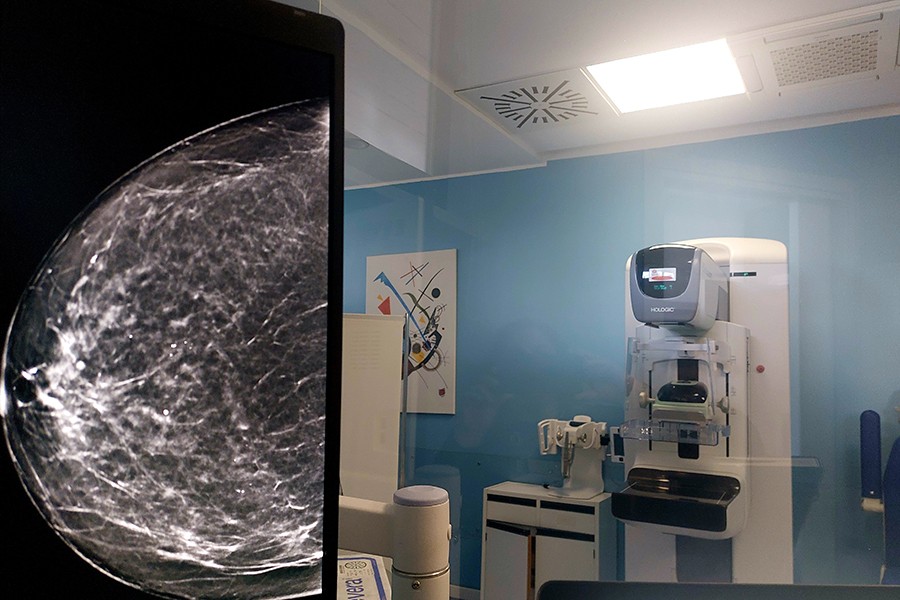

- Mamografía 3D: sistema 3Dimensions

El nuevo sistema 3Dimensions incorpora tecnología de tomosíntesis avanzada que mejora la experiencia y la precisión en mamografía.

Ventajas principales:

• Imágenes más nítidas y de mayor resolución, optimizando la detección de lesiones.

• Mayor comodidad gracias a la superficie de compresión curva que se adapta a la anatomía.

• Flujo de trabajo más eficiente, con exámenes rápidos y tiempos de lectura reducidos.

Estas mejoras refuerzan la confianza diagnóstica y transforman la experiencia del paciente sin comprometer la precisión.